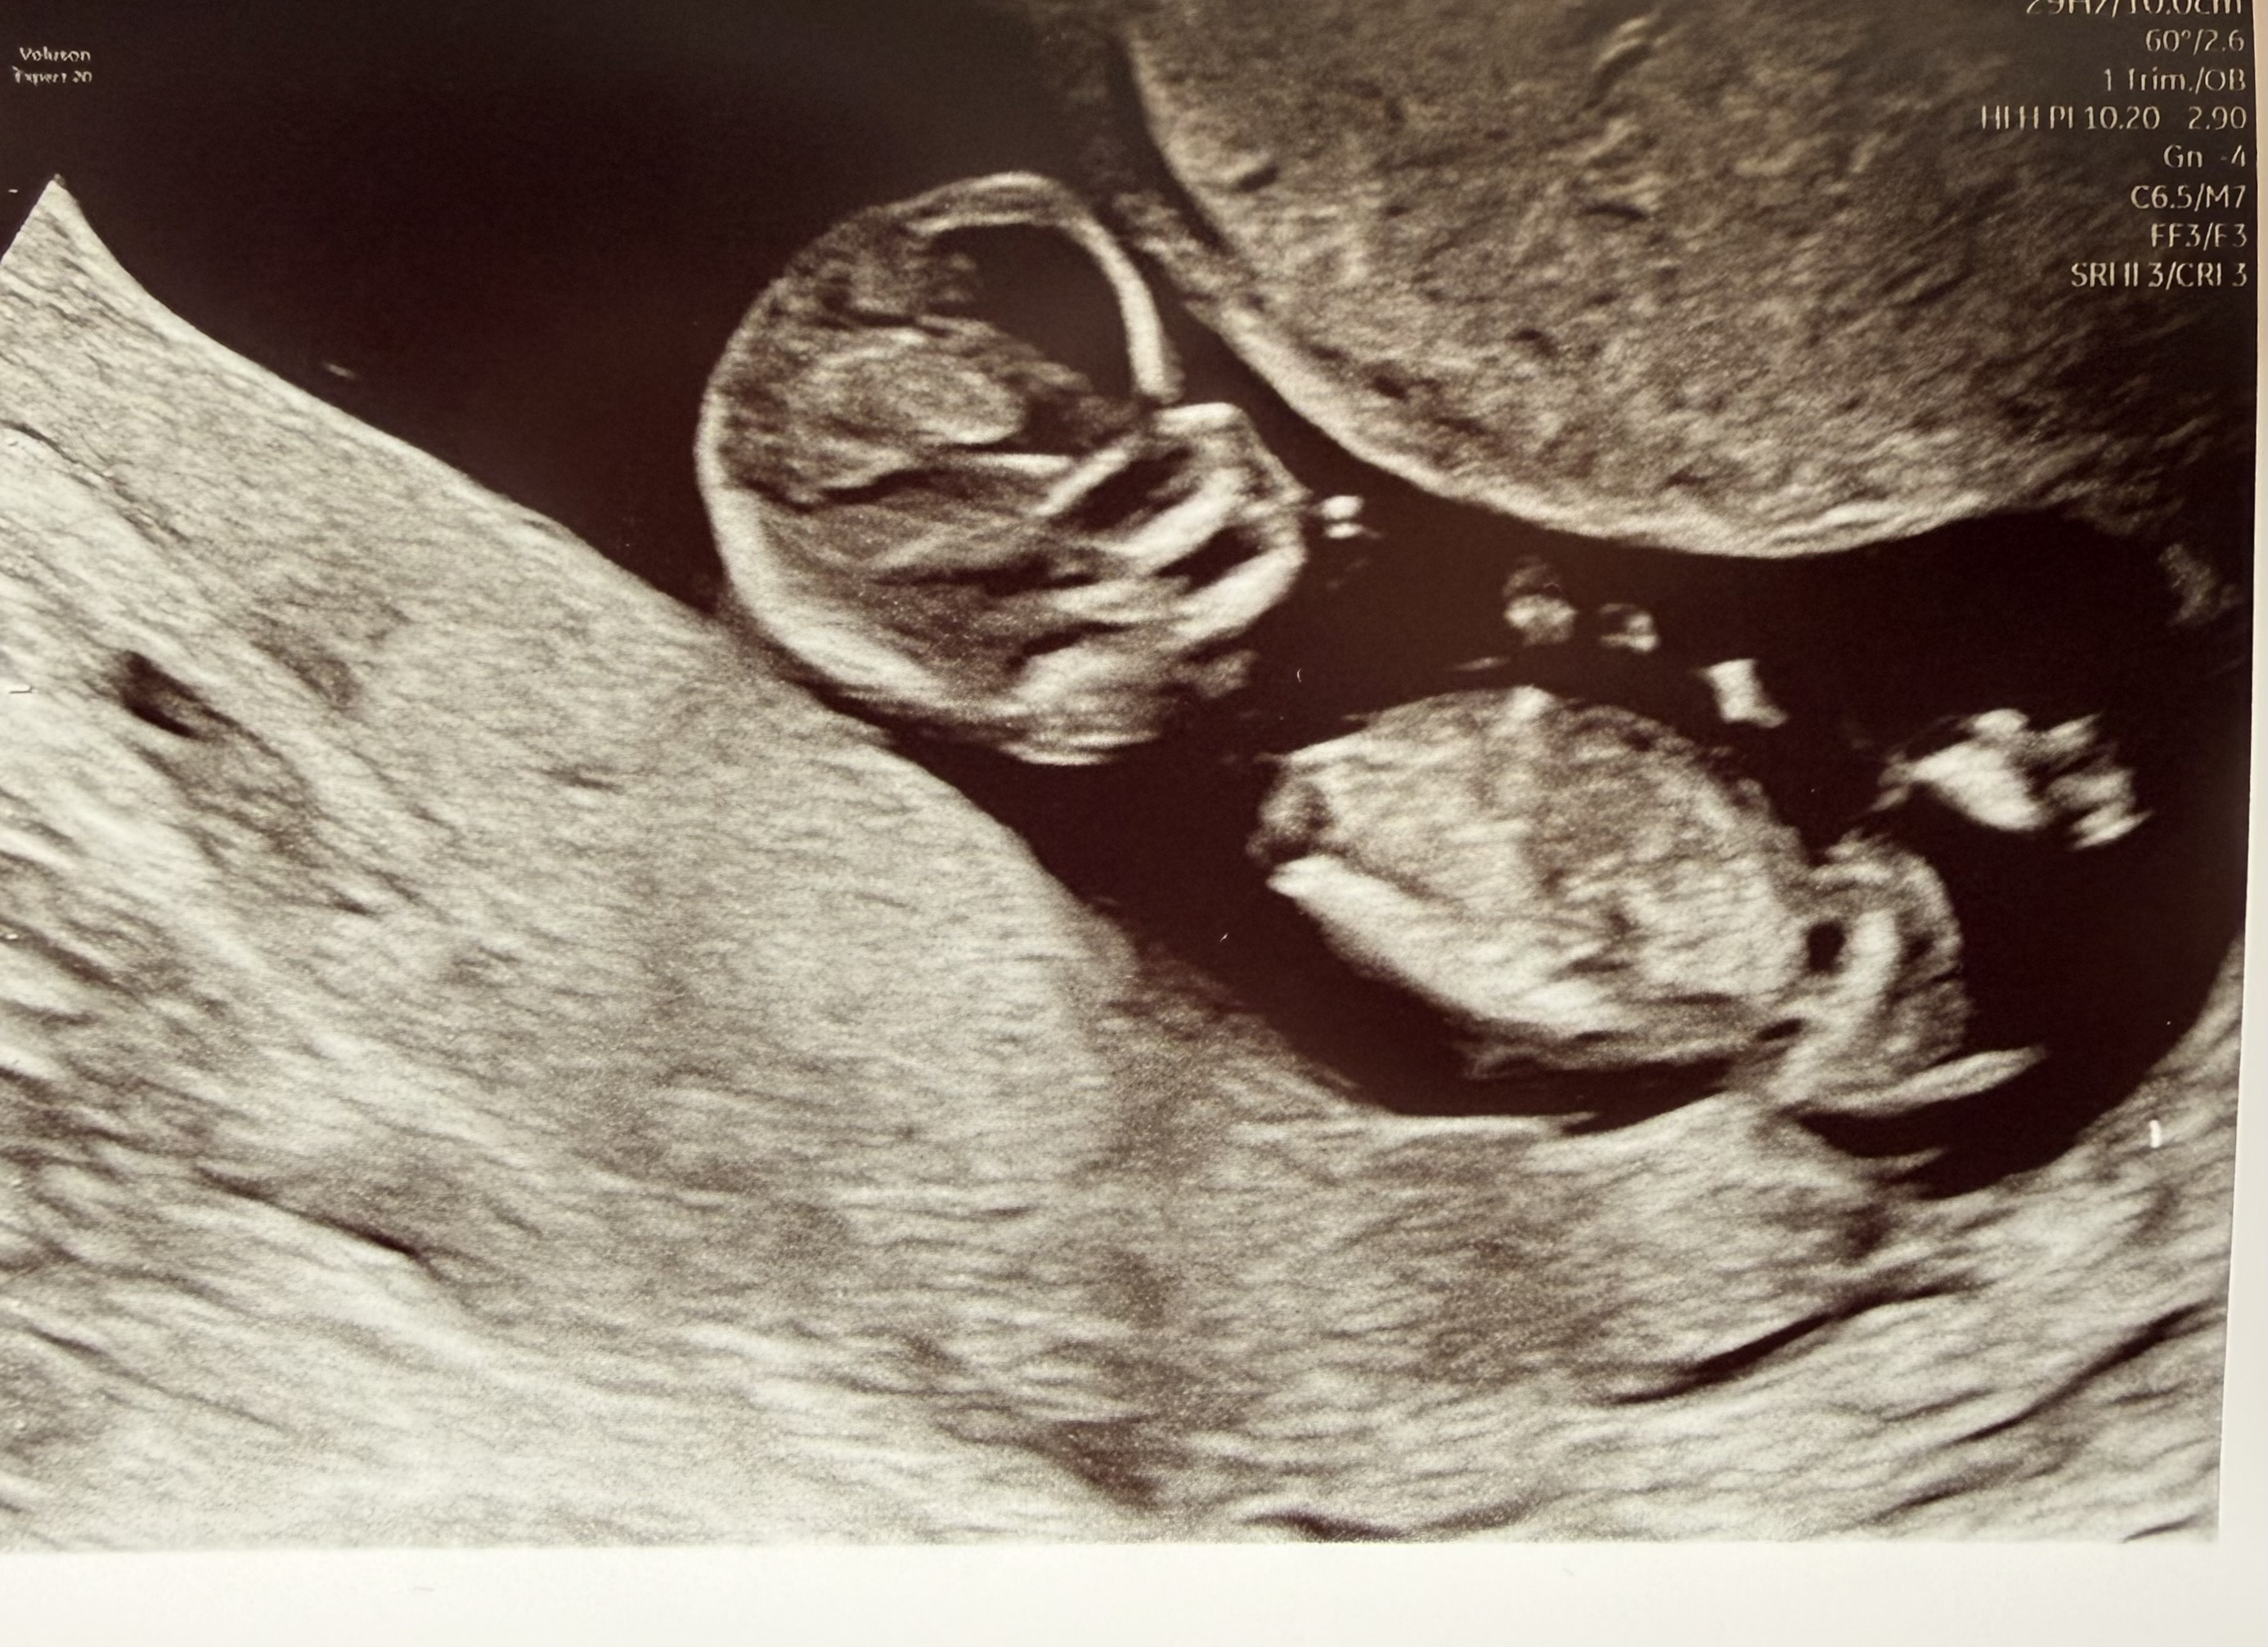

Jestem po badaniu i kamień z serca ♥️

Wszystko w porządku fasolka 6,1cm, wychodzi 12+4 i termin na 4.10 ale Pani doktor powiedziała żeby nie zmieniać i żeby został ten z om czyli 9.10 wcześniej z USG wychodził 6.10

Po badaniu miałam pobraną badanie pappa i teraz czekam na dokładne wyniki

Odrazu zapisałam się na kolejne badania prenatalne 22.05

https://zapodaj.net/plik-jpXrNkR8Bu